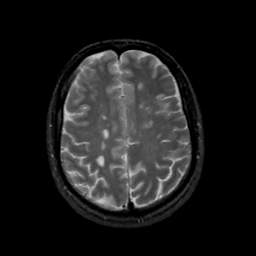

MR Study #17, July 7, 1991 -- Slice #36

[Home][Help][Clinical][Tour 1][Tour 2] Slice 36